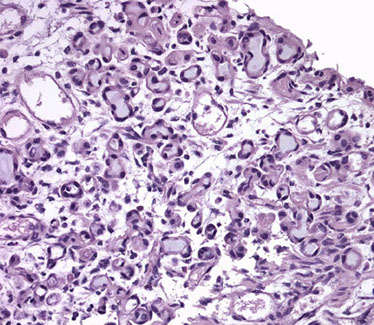

Acinar (Usual) Adenocarcinoma

Can be hard to diff cribriform HG-PIN from cribriform Gleason pattern 3 AC in some cases (usually not too critical)

- in the absence of infiltrating glands, infiltrating AC should only be dx'd on H&E when atypical glands are too large, back-to-back or outside the prostate to be called cribriform PIN

- negative IHC for basal cells also consistent c AC, whereas patchy staining more consistent c PIN

Cytoplasmic features in the Dx of Cancer

Although often overlooked, cytoplasmic features may be essential in dx'ing prostatic ca

- in some AC, the cytoplasm is more amphophilic than the b9 surrounding glands, which are paler or bluish

- the lack of lipofuscin in atypical prostatic glands may help to push the dx to cancer (lipofuscin uncommon in HG-PIN and rare in AC

- abundant cytoplasm c straight luminal borders in larger glands is also a feature of AC, described as a "pseudohyperplastic ca" (but can be seen in atrophy)

Intraluminal Contents in the Dx of Cancer

Crystalloids are dense red structures in various geometric patterns seen on b9 and malig glands

- presence of crystals inversely related to Gleason score

- more freq in cancer than b9 glands, but can also be seen in the b9 condition, adenosis

Blue-tinged mucinous secretions more common in ca, and rarely seen in b9 glands

- dependent on the H&E stain

Pink, dense amorphous acellular secretions seen in ~1/2 cancer, and only occasionally in b9 glands

- should be distinguished from corpora amylacea, which are well-circumscribed round to oval structure c concentric lamellar rings that are prominent in b9 glands and rare in ca

Histologic features specific for Prostate Cancer

3 features which have not been seen in b9 glands, which are in and of themselves dx'ic of ca

1) Perineural invasion

2) Mucinous fibroplasia (collagenous micronodules)

3) Glomerulations

Mucinous fibroplasia - occasionally intraluminal mucinous secretions are so extensive that they become focally organized

- mucinous secretions can displace the epithelium, resulting in atrophic cytoplasm and small pyknotic nuclei, whereby these foci can be hard to see as ca

Glomerulations - glands c cribriform prolif that is not transluminal, but only attaches to one side of the gland (thus resembling a glomerulus)

Perineural invasion - seen in 20% of needle bx of prostate c AC

- if showing PNI hinges on the dx, glands should surround the nerve completely

- must be distinguished from perineural indentation by b9 glands (only partially encompasses nerve)